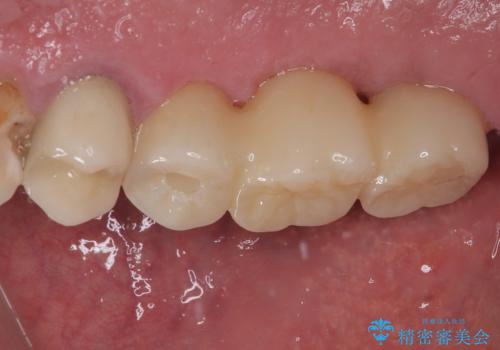

割れてしまった奥歯 抜歯即時埋入インプラントによる短期間治療

- 土台の歯が割れてしまって、歯がグラグラしているとのことで来院された患者様です。

いずれの歯も抜歯が必要な状態であり、抜歯即時埋入によるインプラント治療を行うこととしました。

術後にインプラントの安定値を測定し、十分な値が達成された後、速やかにセラミッククラウンにて補綴治療を行うこととしました。